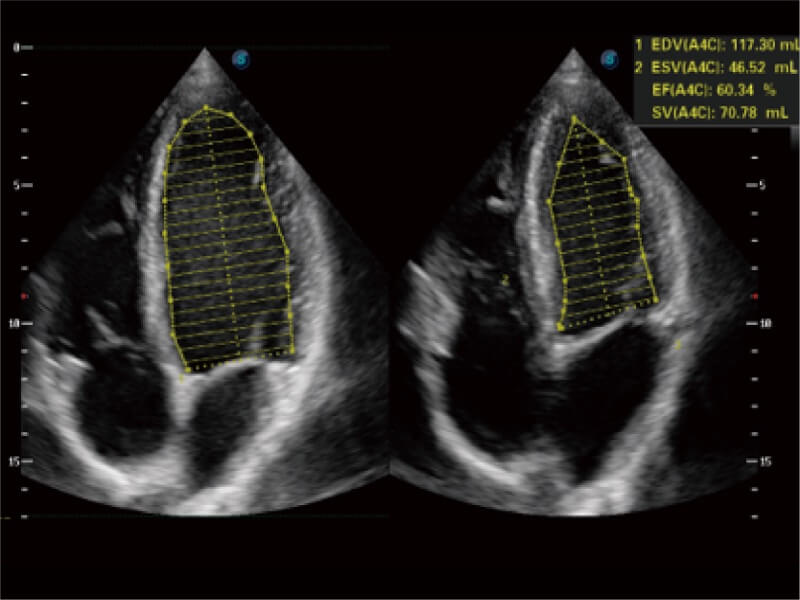

能够基于左心室壁追踪和辛普森法,自动计算射血分数,支持多个可移动点描迹,与手动测量相比,极大节省了动物医生的时间和精力。